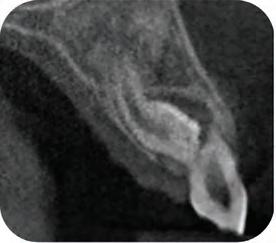

A 77-year-old Caucasian patient presented to the dental clinic after five years without dental care. The clinical findings showed significant bone loss, chronic periodontitis, and loss of some teeth that stabilized the occlusion. The patient reported cold sensitivity in tooth #46, especially when ingesting liquids.

Periapical X-ray confirmed the findings of the clinical examination and root caries was also detected in the distal root of tooth #46, which answered positively to the sensitivity test (Fig.1-2).

The treatment plan began with a focus on returning the patient to adequate periodontal health. In a subsequent session, with improved condition of the periodontium, the restoration of tooth #46 was performed. Under block anesthesia of right inferior alveolar nerve and rubber dam isolation, the amalgam restoration was completely removed and access to the caries cavity obtained (Fig. 3-5). Despite the proximity to the pulp tissue, no exposure occurred, and the class II cavity was fully restored with Biodentine™ (Fig. 6-8).

At two months’ follow-up, no symptoms were reported, no periapical lesion was observed radiographically, and the clinical examination showed normal vitality (Fig. 9-10). Thus, it was decided to perform the definitive restoration, leaving Biodentine™ as the definitive base.

Fig. 1: Initial clinical situation.

Fig. 4: Septomatrix in position.

Fig. 2: Initial X-ray.

Fig. 5: Cavity deep.

Fig. 3: Class II cavity prepared.

Fig. 6: Biodentine™ applied in a Bio Bulk-Fill approach.